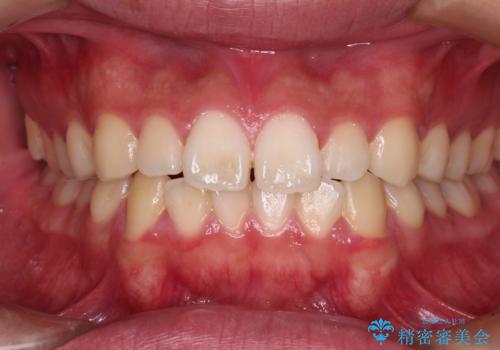

前歯のがたつき 深い噛み合わせを改善したい

ディープバイトとデコボコを解消 インビザライン矯正

デコボコとディープバイトを治したい インビザラインによる矯正治療